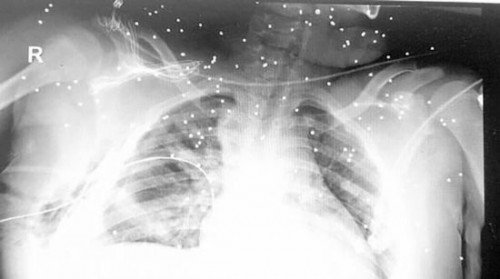

مرآة البحرين: قال والد الطفل محمد السوّاد إن هناك تحسناً طفيفاً في مشكلة النزيف الداخلي التي مرّ بها ابنه، الذي لم يتجاوز الـ13 عاماً، يوم أمس الثلثاء 3 فبراير/ شباط، ومازال مصير عينيه مجهولاً.

وأضاف "كان من المفترض أن يتم نقل ابني من غرفة العناية المشددة إلى غرفة خاصة كوقاية له من انتقال العدوى إليه، وذلك لضعف مناعته في هذا الوضع الصحي السيئ، إلا أننا فوجئنا بنقله إلى الجناح (غرفة عامة) في وسط زحمة الزوار وضجيج الأطفال، ما يجعله أكثر عرضة لانتقال العدوى إليه نتيجة ذلك".

وناشد السوّاد وفق صحيفة الوسط وزارة الصحة تزويده بالتقارير الطبية التي تثبت حالة طفله الحالية للاطمئنان على الوضع الصحي له، ورغبة من الأب في إرسال تلك التقارير إلى الخارج واستشارة بعض المستشفيات، للبحث عن علاج سريع له في حالة توافره في الخارج.

وتابع السوّاد "نحن في قلق كبير لعدم إعطائنا أي تقرير طبي أو تشخيصي بخصوص إصابة عينيّ محمد"، مشيراً إلى أن النيابة العامة قامت باستدعائه مع حسن العجمي (خال الطفل) يوم الإثنين 2 فبراير/شباط الجاري وذلك للاستماع لأقوالهما بشأن الواقعة.